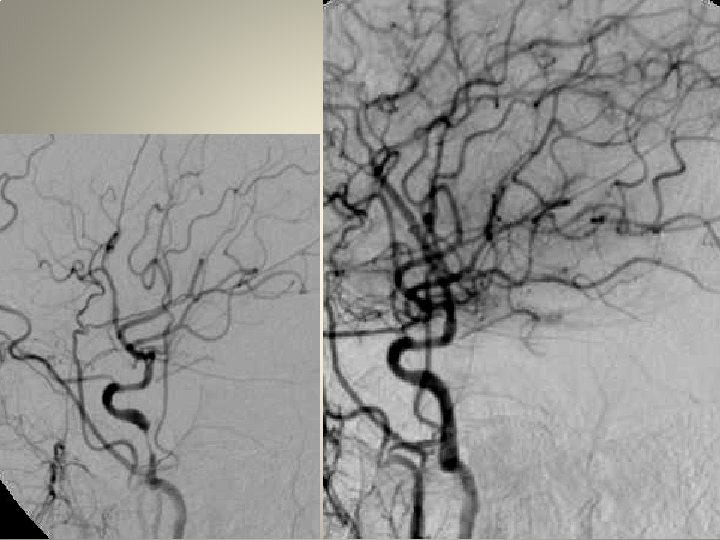

Neden stent? TANDEM lezyon

Neden stent? Distal emboli koruma

Neden stent? Eş zmanlı komplikasyon idaresi

Ülsere plak olgu